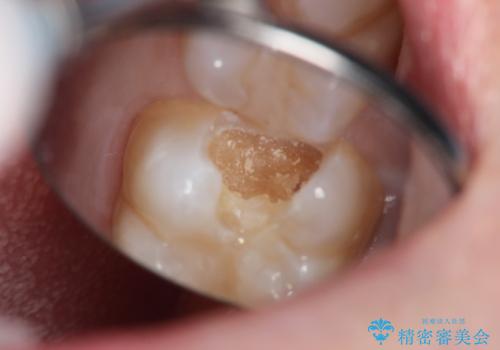

- 虫歯が大きく神経まで達していたので、VPT(歯髄温存療法)を行って細菌感染した部分の神経のみ取り除き、保存可能な神経は保存し被せ物はセラミックインレーで治療を行いました。

昔の歯科医療では神経まで虫歯が達している場合は神経を全て取らなければいけませんでした。しかし現代の歯科医療ではBio-C SealerやMTAセメントの開発により健康な神経を残せるようになりました。

Bio-C Sealerを塗布後、神経に優しい光重合型充填用レジン強化グラスアイオノマーセメントで裏層を行っています。

※術前に神経の状態の検査を行い、術中にもマイクロスコープにて神経の状態を直接確認したうえで残せると判断した場合に行っています。

術中は唾液が入らないようラバーダムシートをかけています。